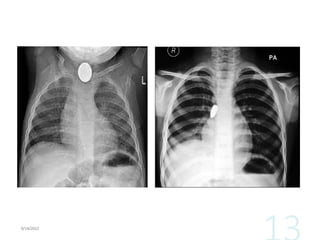

•X-rays, laryngoscopy, or bronchoscopy also may be

performed.

ASSESSMENT AND DIAGNOSTIC FINDINGS •Assessmentof the patient who has a foreign object occluding the airway may involve simply asking the person whether he or she is choking and requires help. •If the person is unconscious, inspection of the oropharynx may reveal the offending object. •X-rays, laryngoscopy, or bronchoscopy also may be performed.